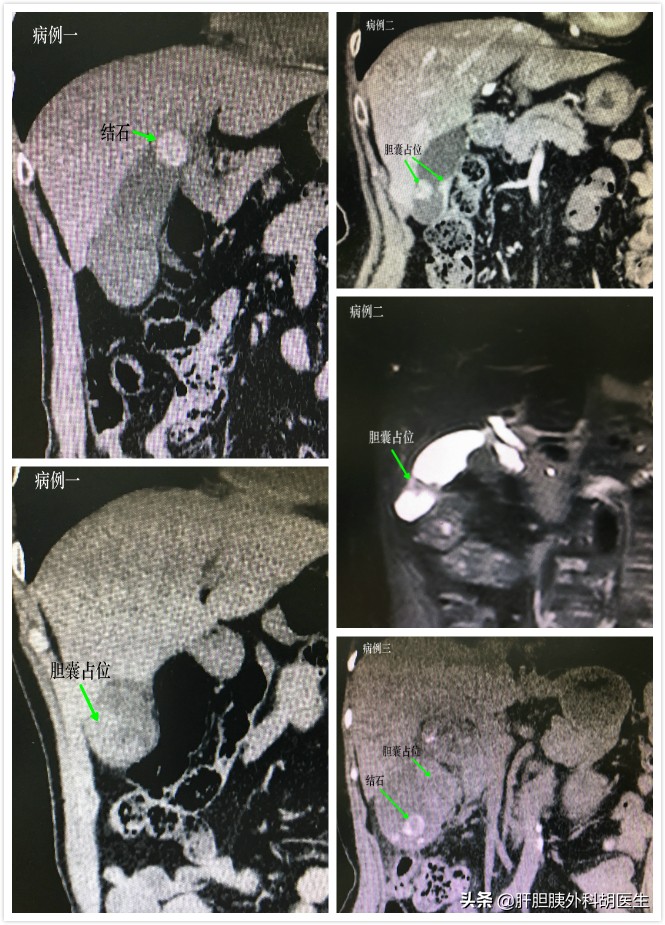

近期连续碰到多例胆囊癌患者,其中4例均有胆囊结石病史多年,未及时治疗,此次出现胆囊炎表现,做了CT发现胆囊占位。顺利施行了胆囊癌根治术,病理明确为胆囊腺癌。另一例有胆囊息肉数十年,定期复查胆囊息肉2-3mm,但半年前查B超提示胆囊息肉明显增大至1.2cm,未引起警惕,此次来查CT已经提示胆囊癌可能。先行胆囊切除,术中冰冻明确为胆囊腺癌。遂施行了胆囊癌根治术。